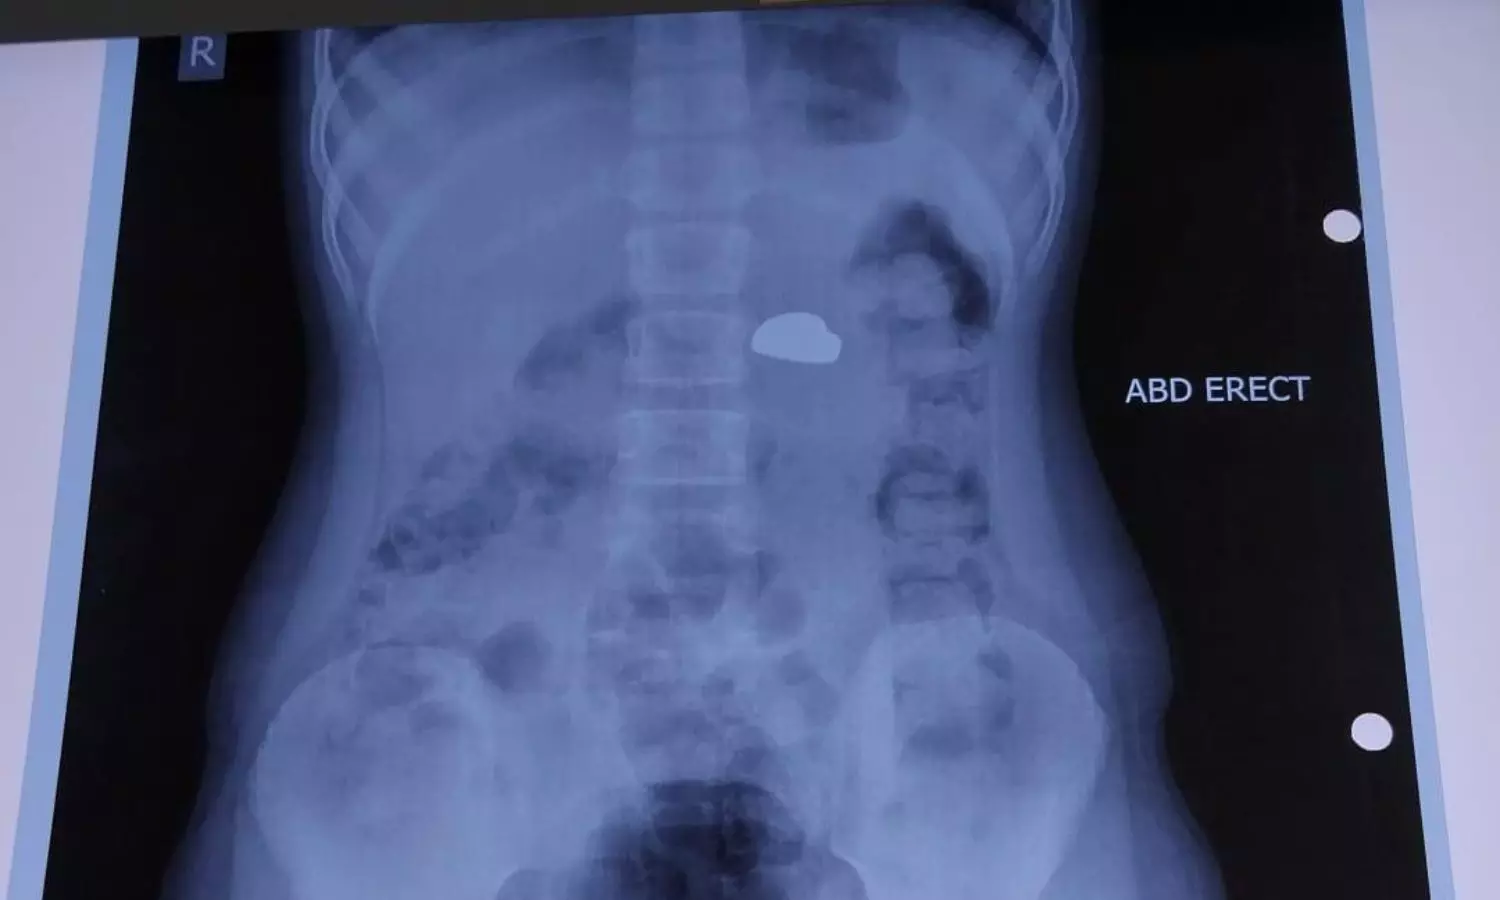

“Magnets are far more dangerous than other swallowed objects. In this case, multiple magnets of varying sizes were found inside the body of the patient, some even bigger than 2cm in diameter.” Dr Agarwal explained. “We first used an endoscope, which is a flexible camera passed through the mouth, to remove three magnets that were still in the stomach and upper intestine.

However, four magnets had already travelled deeper into the intestines and were stuck together. At that point, surgery was the only option. If we had delayed any further, these magnets could have caused holes in the intestine, severe infection, or even death.”